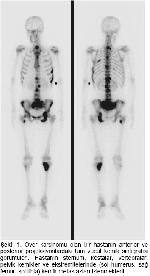

Genellikle yaralanmalar veya göğüs bölgesine alınan darbelerden sonra görülür. Diğer tüm kanserlerde olduğu gibi meme kanserinde evreleme yapılacak tedavinin planlanması açısından vazgeçilmez bir unsur. Kaburga ağrısı genellikle göğüs kafesinin bulunduğu bölgede hissedilen hafif veya şiddetli ağrılardır. Bu metodu uygulamanın en basit yolu bir şeyler öğrendikten sonra gözlerimizi kapatıp büyük bir saray ev ya da kütüphane hayal etmek.

Meme kanserinin sıkça yayılma gösterdiği bölgeler ise kalça ve omurga kemikleri ile akciğer ve karaciğer. Gözlerinizi kapatın ve öğrendiğiniz şeyi görselleştirmeye çalışın. Kemer ilçesindeki bir otelin spor salonunda yeni tip koronavirüs kovid 19 tedbirleri kapsamında gençler ve büyükler kategorilerinde düzenlenen. Halinde güvenlik ve denetim.